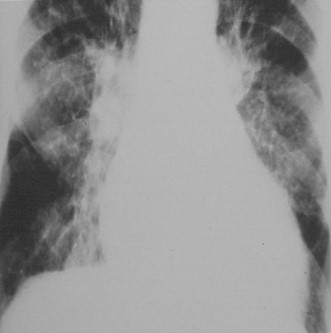

Radiografía de Tórax: se observa cardiomegalia con dilatación de las cuatro cámaras, así como signos de congestión venosa pulmonar. Redistribución superior de la vasculatura pulmonar, aumento del tamaño de los hilios y una disminución generalizada de la vascularización (signo de insuficiencia derecha). Signos de edema pulmonar intersticial. Figura (1,2)

Figura 2. Congestión vascular por insuficiencia cardiaca.